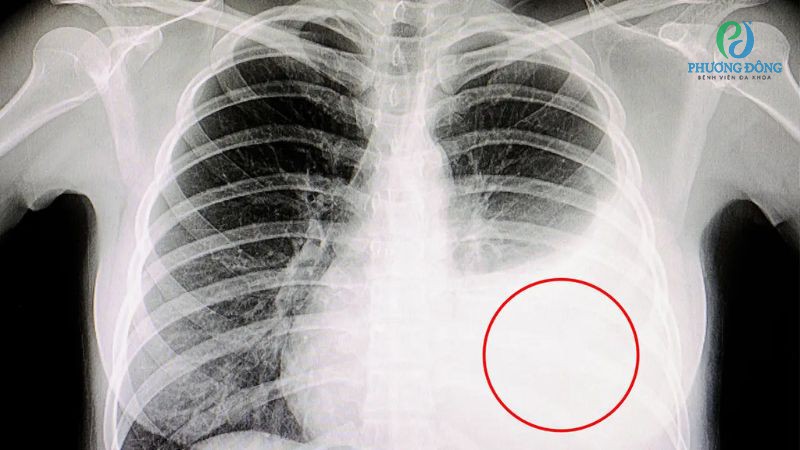

Viêm màng phổi

Cơ hoành bị co thắt là một trong những triệu chứng có thể xuất hiện ở bệnh nhân viêm màng phổi, gây đau nhức kèm theo khó thở. Một số người thậm chí khởi phát sốt, ho, đau lan sang vai hoặc sau lưng.

Viêm màng phổi không chỉ khiến cơ hoành co thắt mà còn khởi phát sốt, ho, đau lan sang vai hoặc lưng

Viêm phổi do vi khuẩn khiến người bệnh đối mặt với loạt triệu chứng tức ngực, sốt cao, khó thở, ho đờm hoặc kèm mủ. Nếu không kiểm soát kịp thời, bệnh lý có thể tiến triển và đe dọa đến tính mạng, đặc biệt ở nhóm trẻ em, người lớn tuổi hoặc có sức khỏe yếu.